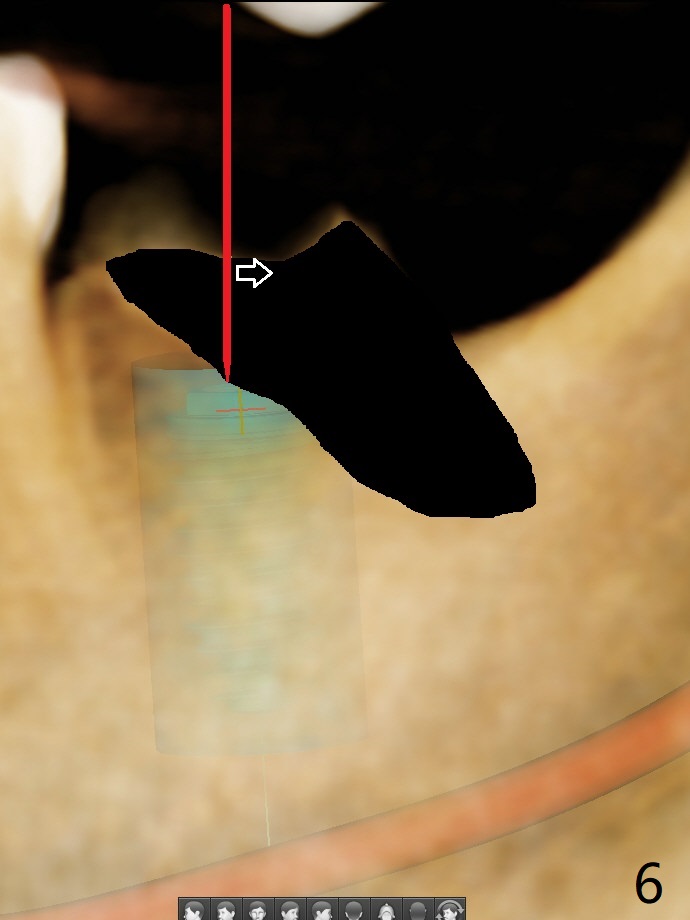

56岁女右侧不好咀嚼,右下7远中龈下龋齿(图一,二),能保留吗?Implant or rct plus crown lengthening, either way is fine, but implant may be more straightforward (Robert). Hi, Jennifer: I love the way you design implant in the mesial slope of the lower 2nd molar (Fig.1,4). When I place an implant free hand, I make sure that the long axis of the implant is 5 mm from the distal surface of the 1st molar (half of the mesiodistal width of the 2nd molar, Fig.5) as long as the implant is not too close to the neighboring root (black dashed line of Fig.5). PAs are taken several times intraoperatively to monitor the distal drifting (Fig.6 open arrow) of the osteotomy (red line). In my opinion, the drifting exists with guided surgery, especially the change of angulation. Can you intentionally move the implant mesially (Fig.7 open arrow) by 0.5-1 mm depending upon bone density or tilt the implant mesial coronally? Thanks for your consideration.